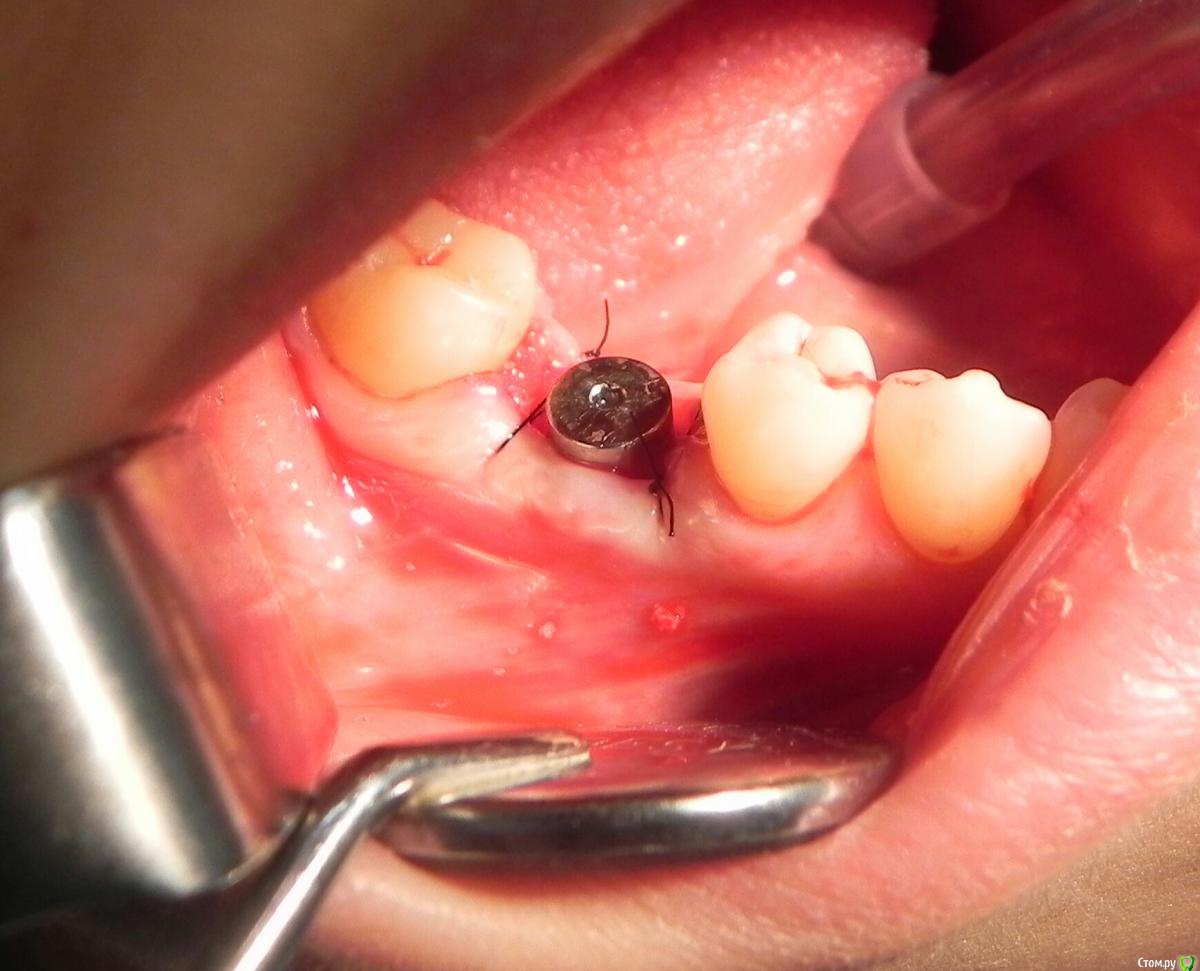

Kostoprav Опубликовано 24 мая, 2016 Поделиться Опубликовано 24 мая, 2016 удалил, вкрутил,графт gen oss, фдм.P.S. сори за плагиат) 3 Ссылка на комментарий

колесников Опубликовано 24 мая, 2016 Поделиться Опубликовано 24 мая, 2016 Всё аккуратно! Только альфа био с фдм не стоит оставлять на 3месяца. Я бы советовал поменять фдм на высотой 2,3 мм, чтобы под десну уходил или взять у sgs анатомический. Ссылка на комментарий

колесников Опубликовано 24 мая, 2016 Поделиться Опубликовано 24 мая, 2016 Формирователь цилиндрический. Не конус. Соединение плоскостное. Плотного запорного кольца из прикреплённой слизистой в основании не будет. Но будет постоянное инфицирование микрофлорой и тонкий слой мягких тканей под фдм не станет хорошим барьером. Растает графт у шейки импланта. Импланты с плоскостным соединение лучше наглухо ушивать . На крайний случай ставить индивидуальный или анатомический фдм. Из практики совет. Ссылка на комментарий